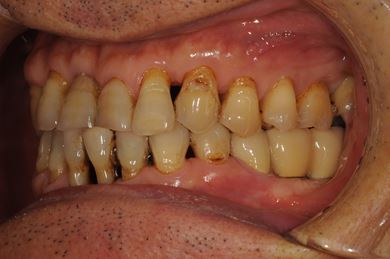

抜歯即日スピードインプラント治療+セラミック治療+歯肉遊離移植術

| 性別/年齢 | 男性 / 64歳 | ||||||||||||||||||||||||||||||||

| 主訴 | 左最奥の下部ブリッジが不安定になっており、奥2本のインプラントを考えたい。 | ||||||||||||||||||||||||||||||||

| 治療内容 | インプラント4本(抜歯即日スピードインプラント)、メタルボンドセラミッククラウン5本、ハイブリッドセラミッククラウン1本(ハイブリッドセラミック用土台1本) | ||||||||||||||||||||||||||||||||